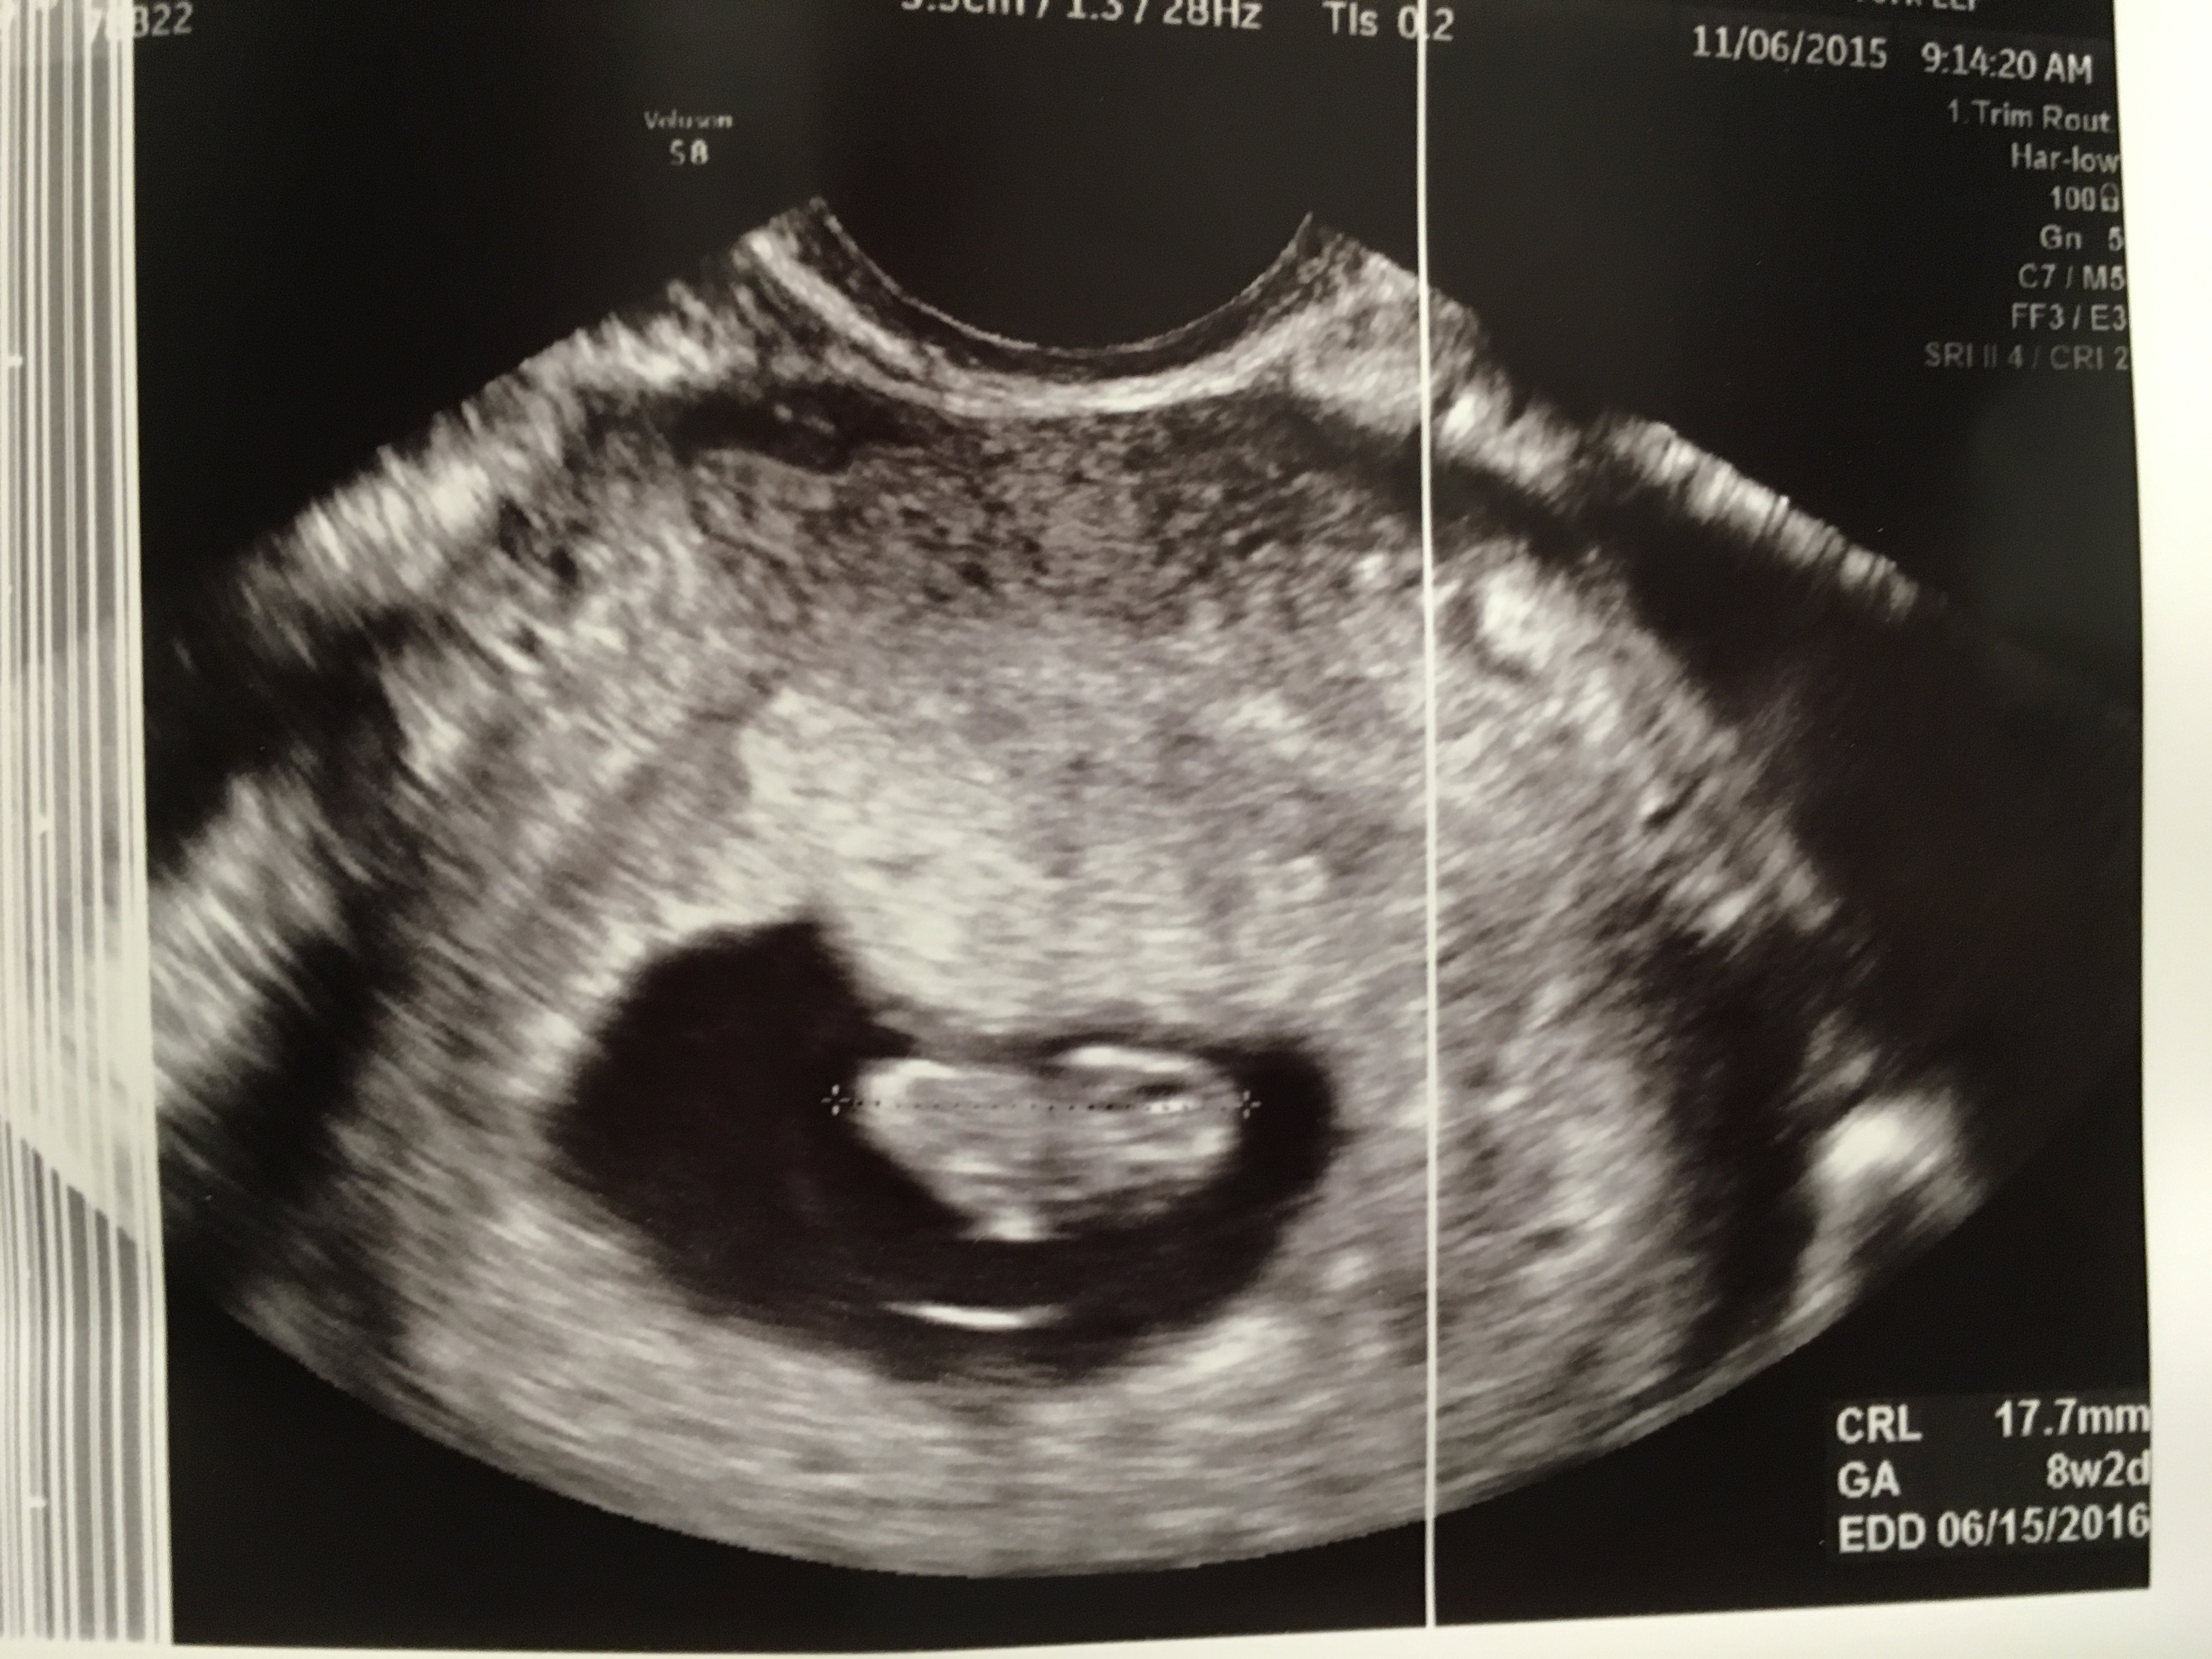

Little Baby! Wow! I'm now 8wks. Had an US two weeks ago and what a change! Saw the heart beating, arms, legs and baby was moving. It's very surreal! Our rainbow baby is due 6-15, day after our two year wedding anniversary. Love seeing everyone's pictures:)